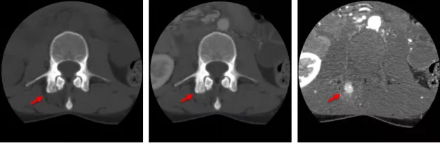

骨智能柔性減影成像功能發(fā)現(xiàn)隱匿骨占位病灶

相比傳統(tǒng)成像方式,肺部柔性減影技術(shù)通過(guò)人工智能,對(duì)平掃數(shù)據(jù)和CT肺動(dòng)脈血管掃描數(shù)據(jù)進(jìn)行智能比對(duì),解碼并識(shí)別各個(gè)器官(肺、氣管、肺動(dòng)脈、肺靜脈、主動(dòng)脈等)的空間位置,并在三維空間中進(jìn)行體素級(jí)的柔性配準(zhǔn),從而極大提升了不同序列數(shù)據(jù)的空間位置的一致性。通過(guò)肺部柔性減影技術(shù)可得到肺強(qiáng)化碘圖,可以顯示出傳統(tǒng)CTPA圖像看不到的小栓塞病變,提高了栓塞檢出率,其結(jié)果甚至可與SPECT吻合。

肺智能柔性減影成像功能發(fā)現(xiàn)亞段肺栓塞